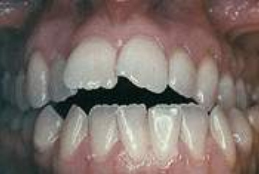

Durch zu

viel Daumenlutschen oder Sauger

(Flaschensauger oder Nuggi) ergibt sich

die Zahnfehlstellung des "offenen Biss"

bei den bleibenden Zähnen. [5]